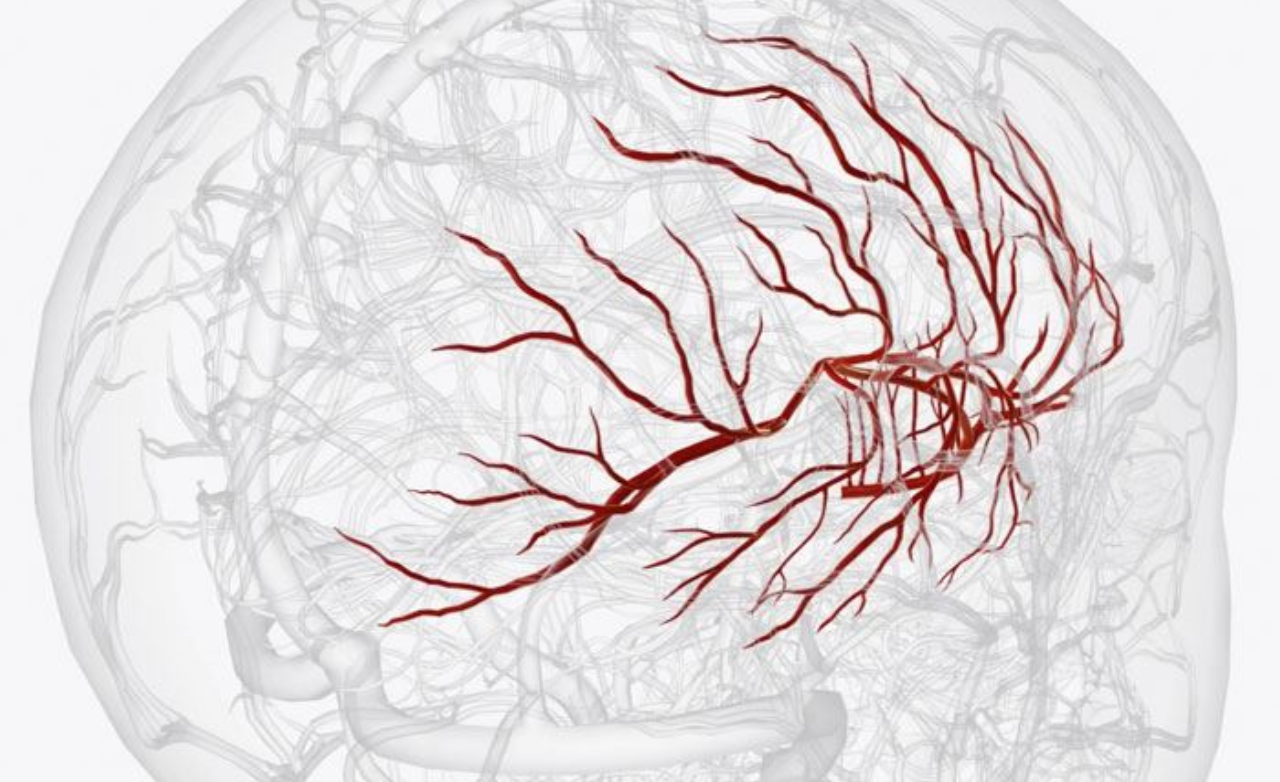

Abnormal tangling of arteries and veins in the brain, disrupting flow, causing headaches, seizures, or hemorrhage.